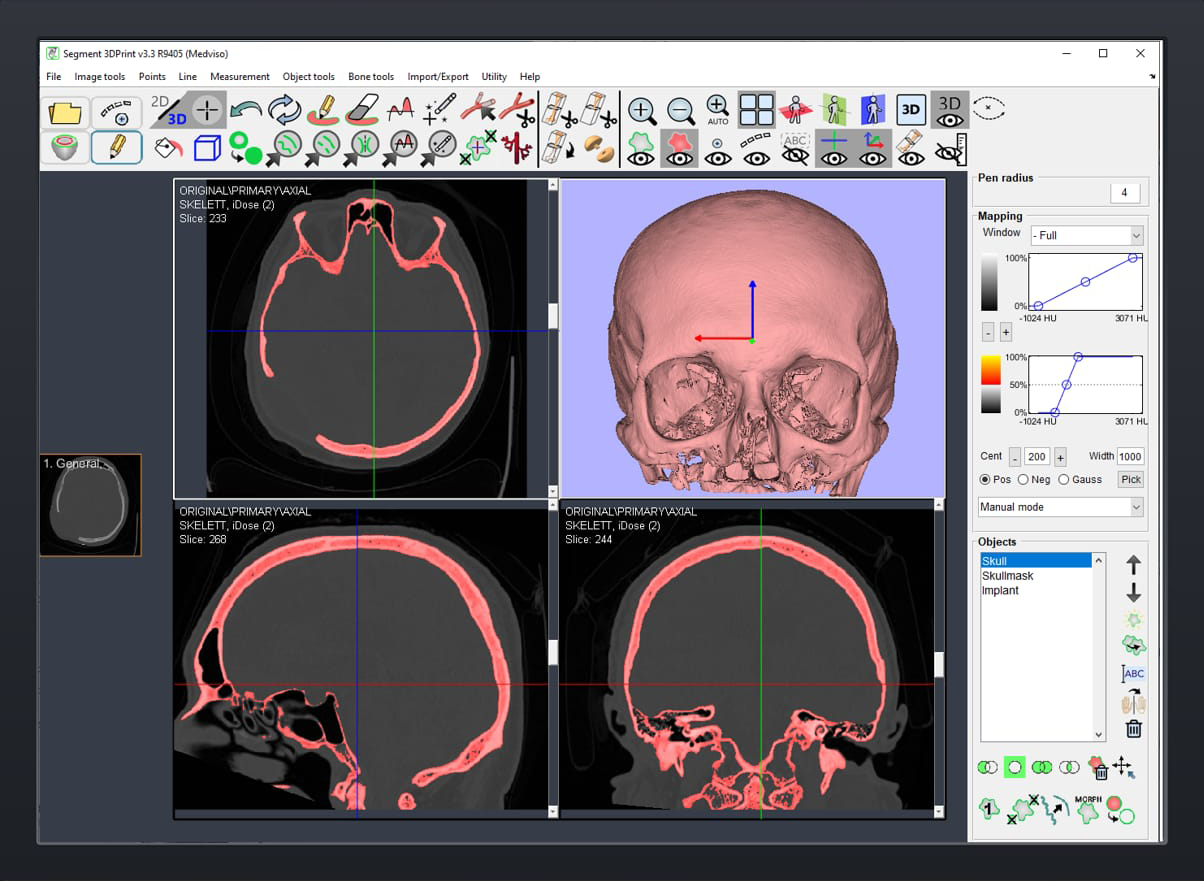

Designing with segmentation software based on AI.

CT scan images to be exported in DICOM format

Orientation : Head Backward

Slice thickness : Maximum 1.0 mm with interslice distance 1mm or less.

Feed per rotation : Maximum 1.0 mm

Gantry tilt/Oblique angle: 0 degree

Matrix Resolution : 512 X 512

Reconstruction algorithm : Bone or high resolution

Scout length : Cover entire

Skull Scan mA : 175 (not binding)

Scan KV : 130 (not binding)